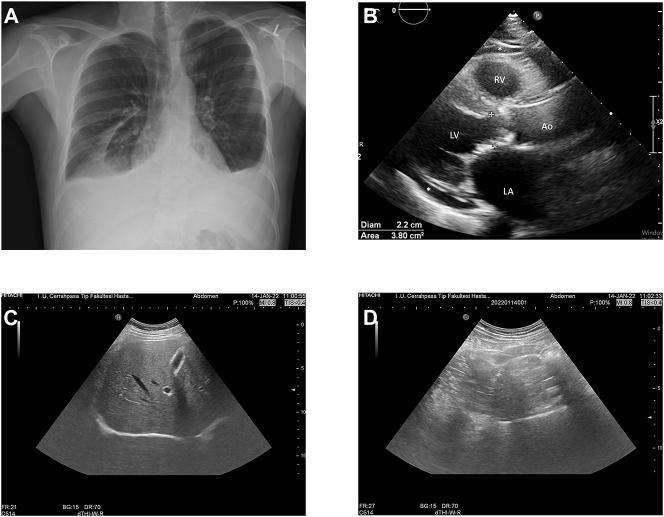

Objectives: Pleural effusion (PE) is the most frequent pulmonary complication of dasatinib, a tyrosine kinase inhibitor (TKI). Concurrent pericardial effusions have been reported in about one-third of the cases. In this study, we aimed to investigate ascites generation in chronic-phase chronic myeloid leukemia (CML-CP) patients developing PE under dasatinib.

Methods: We conducted a cross-sectional study to evaluate whether pericardial effusion and ascites accompany PE in CML-CP patients treated with dasatinib. For this purpose, consecutive patients with CML-CP who developed PE under dasatinib therapy have been evaluated with chest X-ray, transthoracic echocardiography, and abdominal ultrasonography.

Results: There were seven patients, and the median age was 50 years (range, 31-73 years). Most of patients were male (n=5). All patients received imatinib as first-line TKI. Six patients received dasatinib following imatinib failure in second line. The median duration from dasatinib initiation to PE generation was 58 months (range, 8-135 months). Consequently, four patients had grade 1 pericardial effusion, and no patient had ascites.

Conclusions: In our small study, dasatinib-related PE was associated with low-grade pericardial effusion but no ascites. There are hypothetical explanations of this phenomenon including the simultaneous activation/inhibition of kinases; however, more research needs to be performed on this topic.